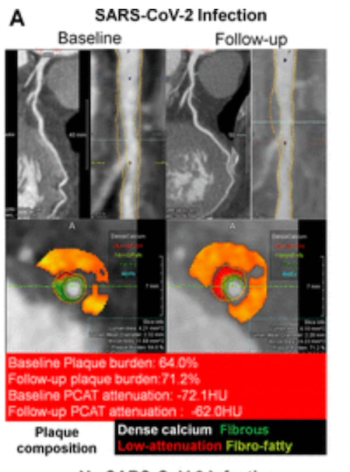

Prior COVID-19 infection was associated with a 28 percent higher progression of total percent atheroma volume (PAV) annually and over a 5 percent higher incidence of high-risk plaque in patients with coronary artery lesions, according to CCTA findings from a new study.